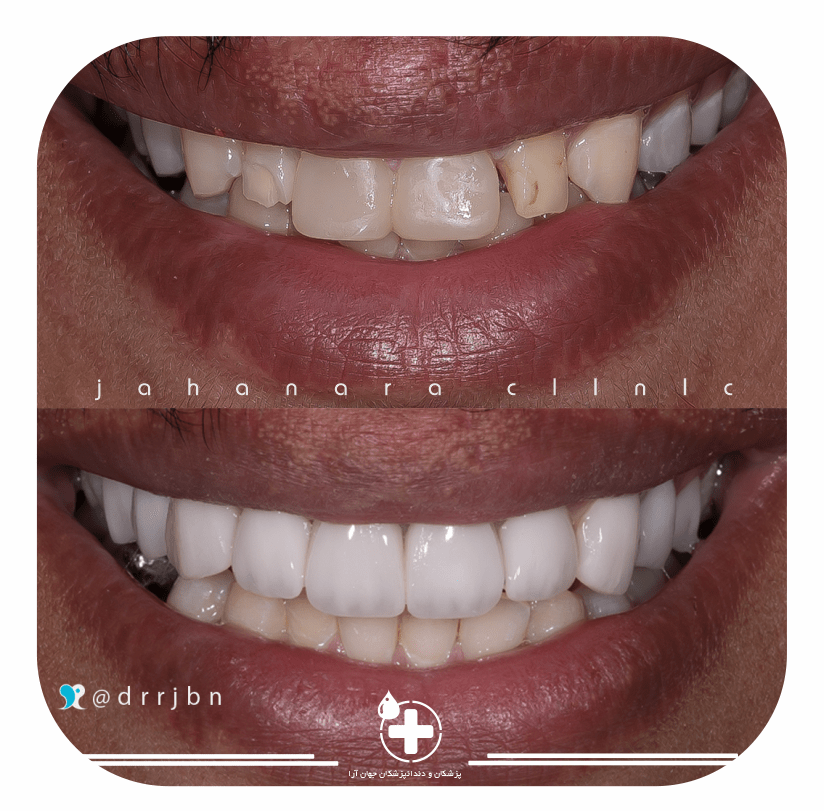

Cosmetic Dentistry

بهترین لمینت ونیز با کامپوزیتهای آمریکایی و IPS.

حتما نمونه های قبلی را ببینید.Periodontal Disease

اصلاح طرح لبخند

اصلاح طرح لبخندچون لبخند شما مهم است

لمینت کامپوزیتی و سرامیکی

لمینت کامپوزیتی و سرامیکیاوج کیفیت با امکان مدیریت هزینه